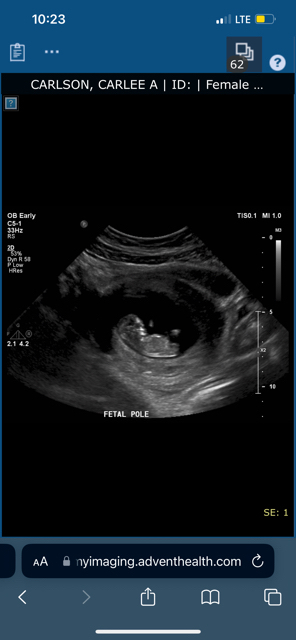

This is my 12 weeks scans any guesses?? I’d love some insight